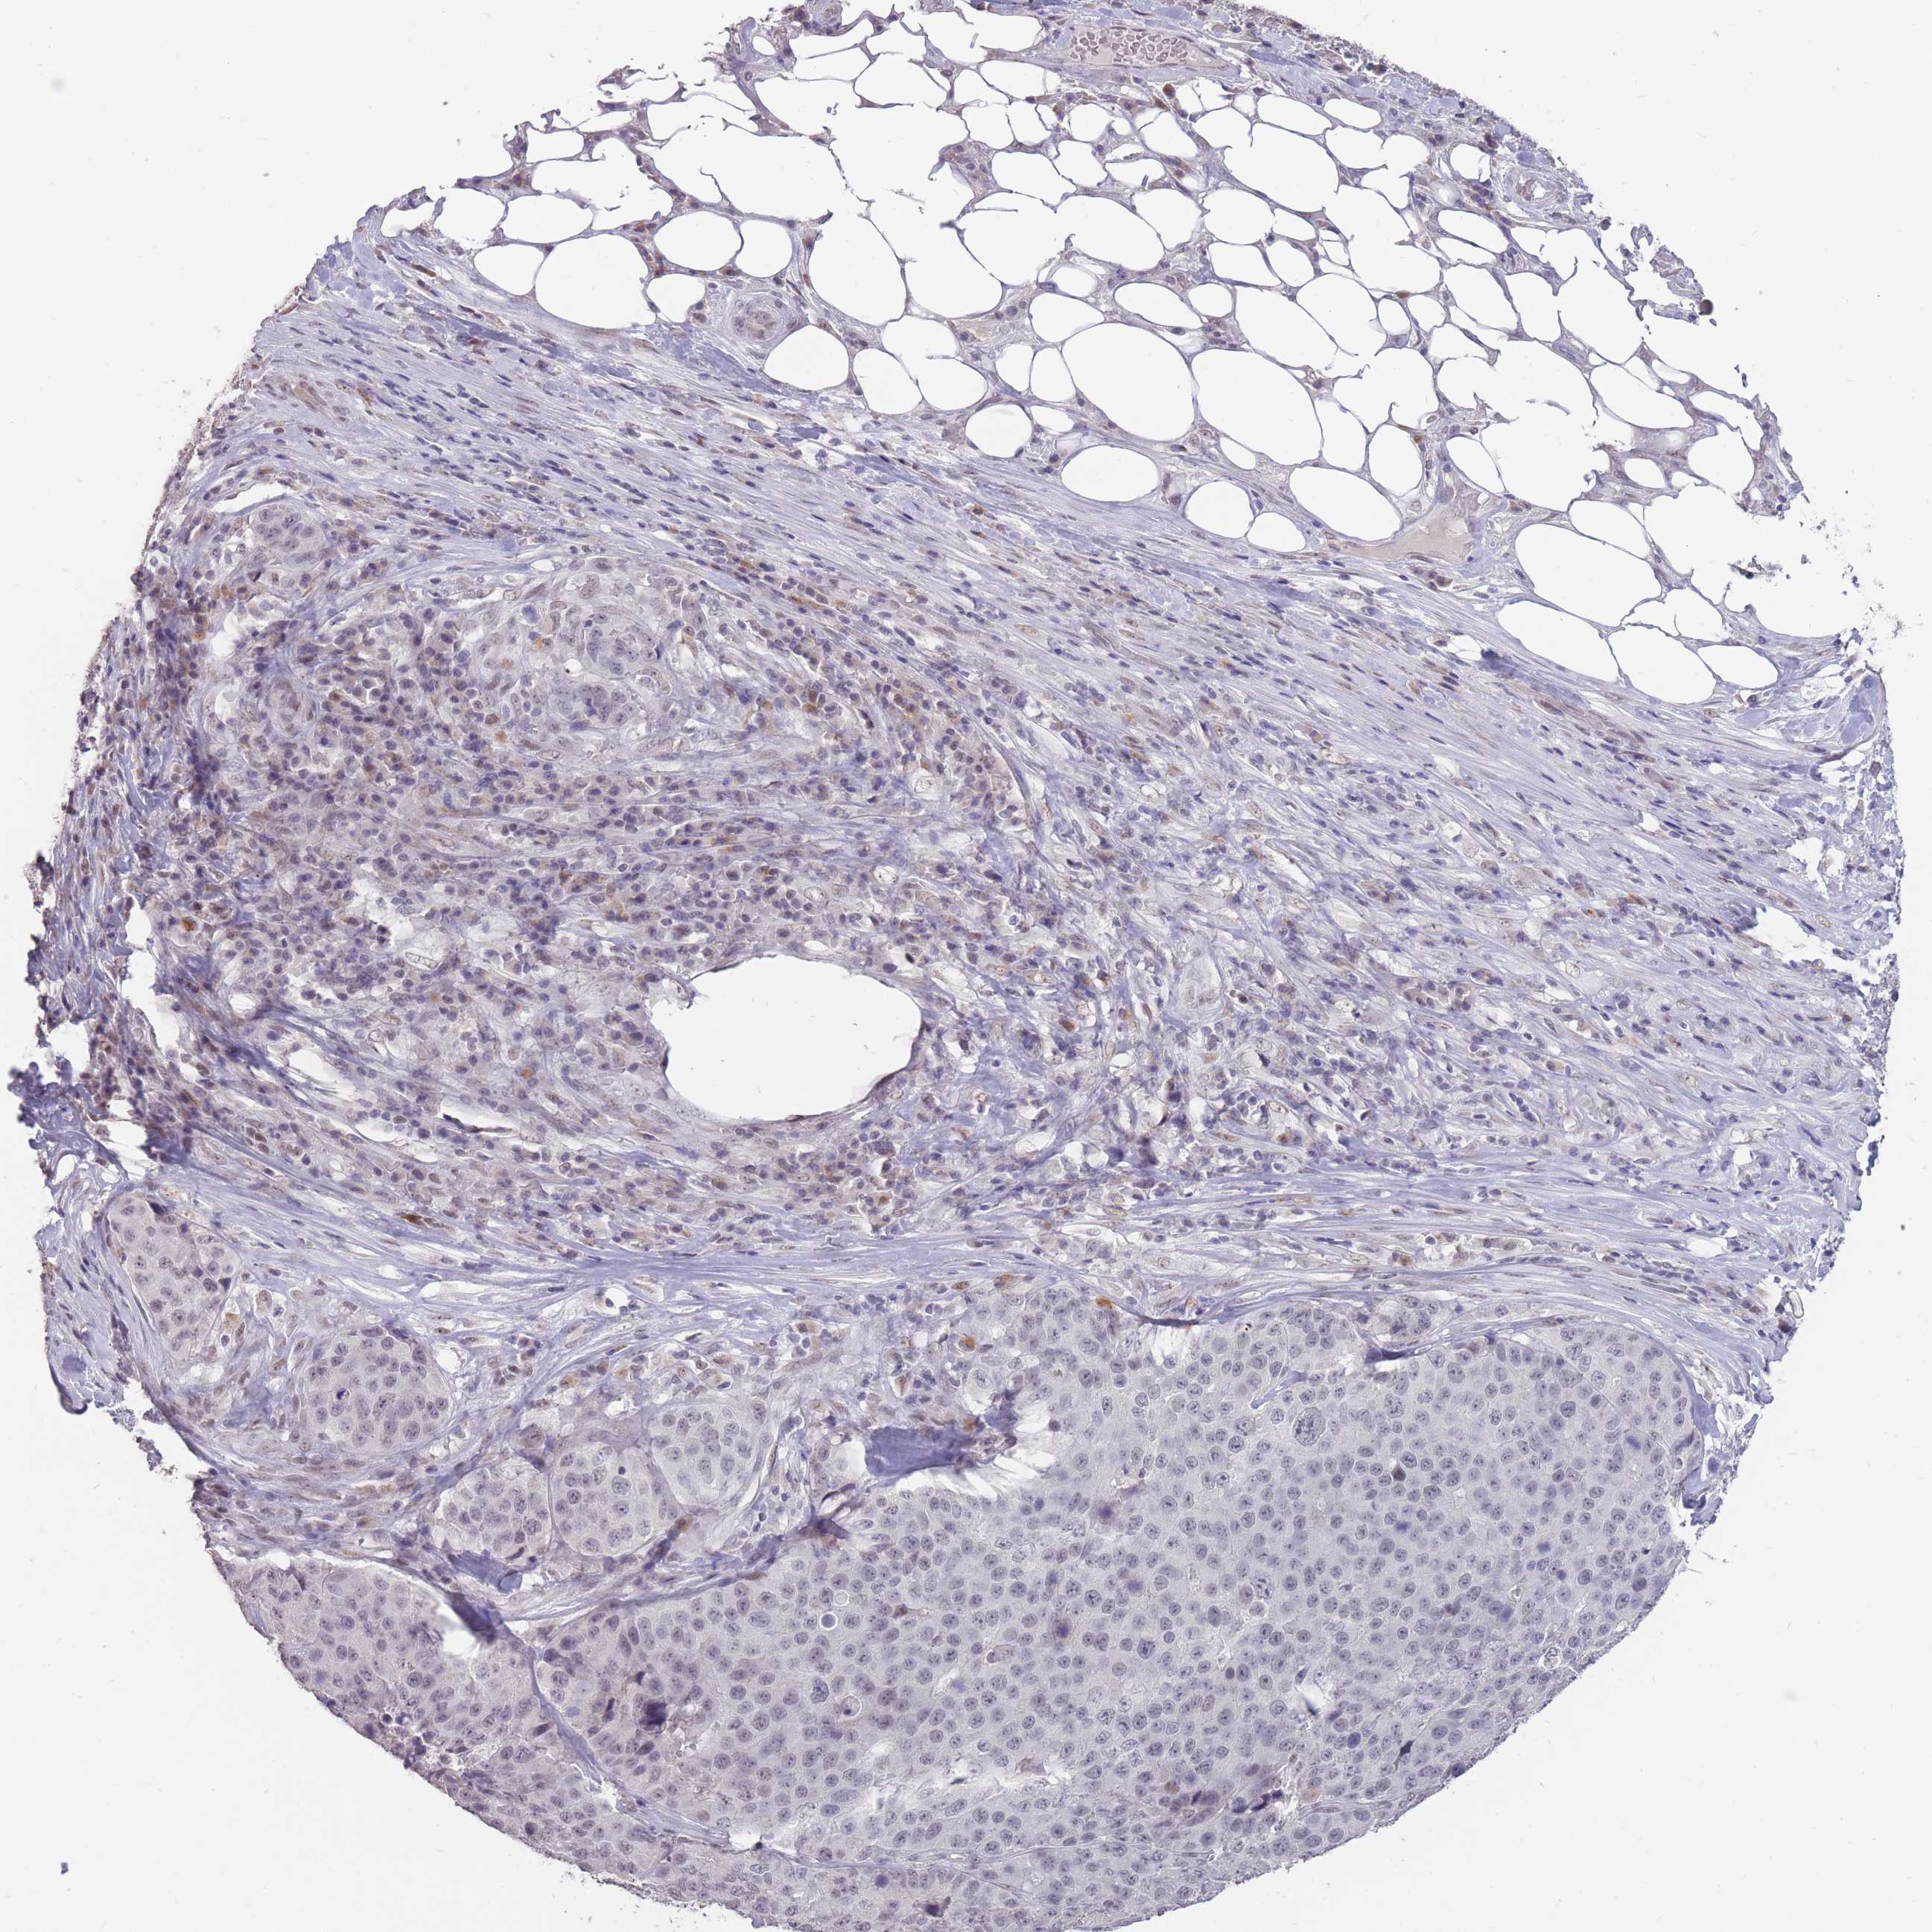

STOMACH CANCER - Protein expressioni

A mouse-over function shows sample information and annotation data. Click on an image to view it in a full screen mode. Samples can be filtered based on level of antibody staining by selecting one or several of the following categories: high, medium, low and not detected. The assay and annotation is described here.

Antibody stainingi

Antibody staining in the annotated cell types in the current human tissue is reported as not detected, low, medium, or high, based on conventional immunohistochemistry profiling in selected tissues. This score is based on the combination of the staining intensity and fraction of stained cells.

Each image is clickable and will lead to virtual microscopy that enables deeper exploration of all samples and also displays staining intensity scores, fraction scores and subcellular localization as well as patient and tissue information for each sample.

Antibody HPA046290

Antibody HPA049475

Antibody CAB046477

Staining

High

Medium

Low

Not detected

Intensity

Strong

Moderate

Weak

Negative

Quantity

>75%

75%-25%

<25%

None

Location

Nuclear

Cytoplasmic/membranous

Cytoplasmic/membranous,nuclear

Adenocarcinoma, NOS